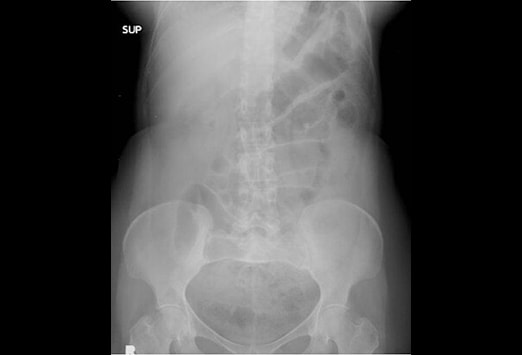

Nonspecific Bowel Gas Pattern. The interpretation nonspecific abdominal gas pattern should be avoided. Mild localized ileus or sentinel loop. Page Contents1 OVERVIEW2 ORIENTATIONS USED FOR ABDOMINAL X-RAYS3 ANATOMY ON ABDOMINAL X-RAY4 APPROACH GECkoS5 GAS PATTERN INTRALUMINAL6 EXTRALUMINAL GAS7 CALCIFICATIONS8 SOFT TISSUE MASSES OVERVIEW This page is dedicated to providing a guide on the approach to interpreting an abdominal X-ray. Posted 532012 330 PM GMT -7 Has anybody has this.

In patients with acute abdominal symptoms who have normal or abnormal but nonspecific bowel gas pattern on abdominal plain films CT is recom- mended see Fig. ICD-10-CM Diagnosis Code K59. Nonspecific bowel gas pattern. It is Non-Specific Bowel Gas Pattern. A physiological stool burden means you have a normal amount of stool in your colon. The radiology report is the primary means of communication between the radiologist and the referring physician.

Functional disorders of stomach K31- ICD-10-CM Diagnosis Code K59. Hover onoff image to showhide findings. This phrase is often used when the bowel gas pattern is not specific for a small bowel obstruction. We found the definition to be dichotomous and asynchronous between radiologists and their referring physicians. Furthermore there is a wide range of meaning of the term among radiolo- gists because the criteria used are individual and sub- jective. 6 A recent survey of community-based teaching hospital radiolo- gists showed that 70 of the radiologists used this term.

Bowel gas patterns may point to an underlying cause bowel gas patterns include. This phrase is often used when the bowel gas pattern is not specific for a small bowel obstruction. Small bowel air usually appears as multiple small randomly distributed gaseous foci scattered throughout the abdomen. I suggest you look the article by. Emergency R a d i o l o g y M a y J u n e 1996 further.

The bowel gas pattern is normal. It is Non-Specific Bowel Gas Pattern. Infectious Disease 33 years experience. This doesnt help the ordering physician much except to tell him to use his clinical suspicion to guide further workup. Page Contents1 OVERVIEW2 ORIENTATIONS USED FOR ABDOMINAL X-RAYS3 ANATOMY ON ABDOMINAL X-RAY4 APPROACH GECkoS5 GAS PATTERN INTRALUMINAL6 EXTRALUMINAL GAS7 CALCIFICATIONS8 SOFT TISSUE MASSES OVERVIEW This page is dedicated to providing a guide on the approach to interpreting an abdominal X-ray.

Dilatation 3cm of the small bowel is considered abnormal however the longer the segment of bowel that is dilated the more likely bowel dilatation represents a genuine obstruction. Functional disorders of stomach K31- ICD-10-CM Diagnosis Code K59. Change in bowel habit NOS R194. Im only addressing the first question. Nonspecific bowel gas pattern.

X-ray The bowel gas pattern appears unremarkable. It basically means that the appearance of bowel is unclear on the X-ray and can be normal or abnormal. Page Contents1 OVERVIEW2 ORIENTATIONS USED FOR ABDOMINAL X-RAYS3 ANATOMY ON ABDOMINAL X-RAY4 APPROACH GECkoS5 GAS PATTERN INTRALUMINAL6 EXTRALUMINAL GAS7 CALCIFICATIONS8 SOFT TISSUE MASSES OVERVIEW This page is dedicated to providing a guide on the approach to interpreting an abdominal X-ray. ICD-10-CM Diagnosis Code K59. See the page on normal Bowel Gas Pattern.

See the page on normal Bowel Gas Pattern. Non-Specific Bowel Gas Pattern - How is Non-Specific Bowel Gas Pattern abbreviated. CONCLUSIONS Radiologists use the term nonspecific gas pattern to denote a gas pattern that is not quite normal but that does not fulfill the criteria of a more specific diagnosis such as small bowel obstruction. The radiology report is the primary means of communication between the radiologist and the referring physician. The term nonspecific abdominal gas pattern should be abandoned because it may signify a normal condition or a pathologic state.

The interpretation nonspecific abdominal gas pattern should be avoided. We found the definition to be dichotomous and asynchronous between radiologists and their referring physicians. Furthermore there is a wide range of meaning of the term among radiolo- gists because the criteria used are individual and sub- jective. This type of scan is also sometimes. We all have gas in our bowels and a non obstructive bowel gas pattern means it looks like it should look.

Slide 2 of 3. A normal small bowel gas pattern varies from no gas being visible to gas in three or four variably shaped small intestinal loops. NSBGP is a shorter form of Non-Specific Bowel Gas Pattern. Nonspecific bowel gas pattern. We all have gas in our bowels and a non obstructive bowel gas pattern means it looks like it should look.